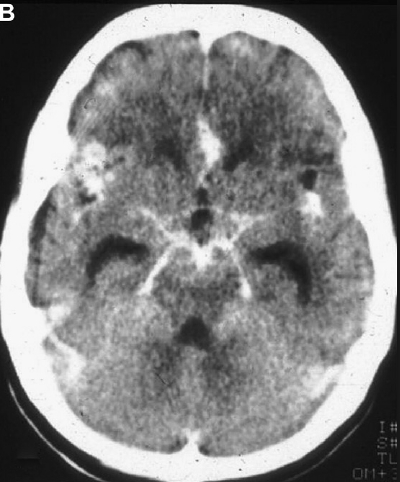

diagnosis: The CT scan with contrast can be an excellent clue for diagnosing tuberculous meningitis. Exudate (enhancement) in the basal cisterns that shows enhancement by contrast material is typical; tuberculomas, ringed lucencies, edema, and infarction can be apparent; and hydrocephalus can develop. Confirmation with culture is mandatory. The x-ray of the chest will be likely to show signs of pulmonary tuberculosis.